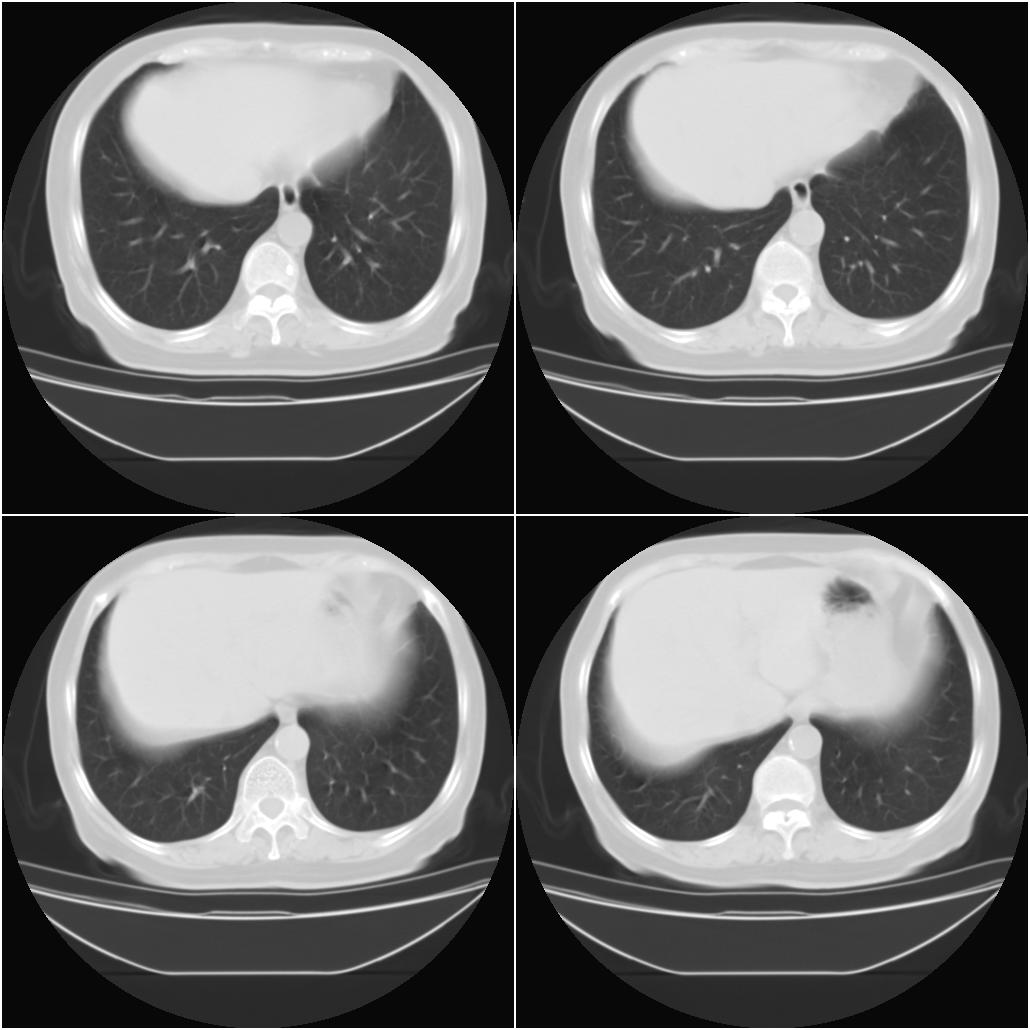

以下是引用sxlcbc在2007-12-23 4:27:00的发言:[br]气管源性肿瘤觉得有点不靠谱啊,看上去气管是受压改变的。更像是上段食管的改变,周围淋巴结肿大,食管受压。看看以下六幅图片:[br]不过,有一点不好理解:食管肿瘤应该有食道症状的,再说食管癌出现周围这么大的淋巴结也不多见啊,如果考虑淋巴瘤倒是更合理一点,这样气管,食管受压改变也许更合理一些。[br][br]